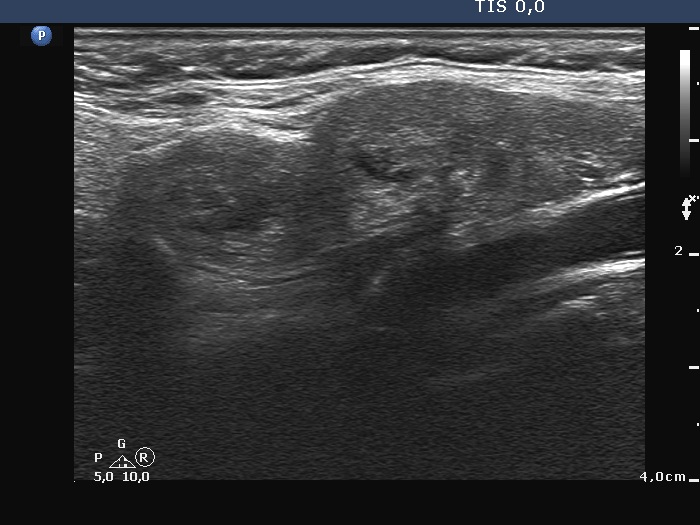

Ultrasonography. There was no thyroid tissue in the thyroid beds. Approximately 7 cm above the thyroid in the left side of the neck there were multiple, moderately hypoechoic lesions which presented tiny cystic areas. They had vascularity but did not have capsule.